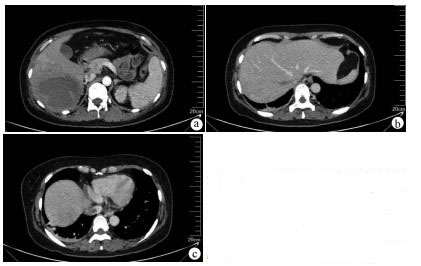

Differential diagnosis and treatment of jaundice after comprehensive treatment of advanced primary liver cancer: A case report

Abstract(920) HTML (401) PDF (2088KB)(73)

Abstract: